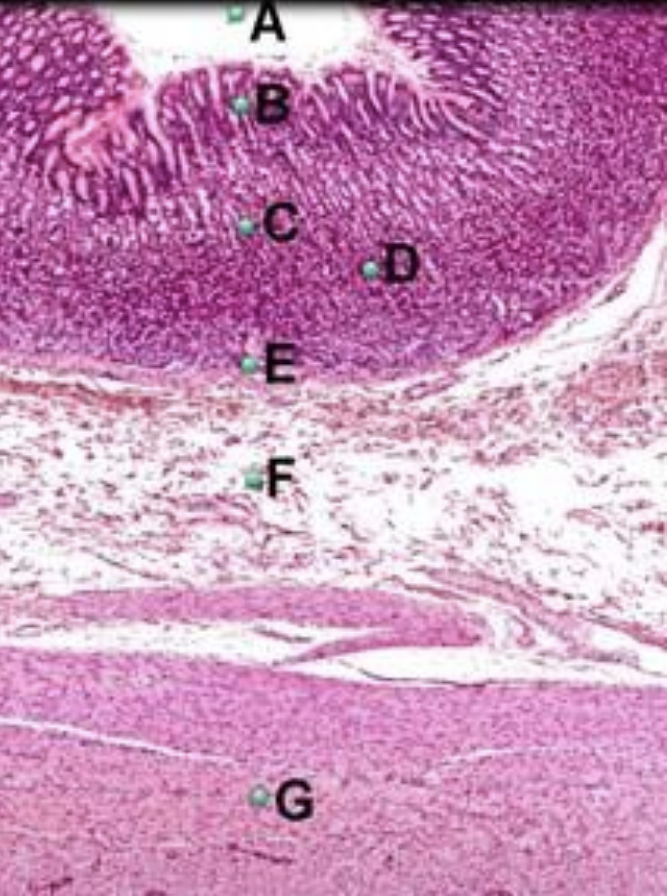

Part A?

esophagus

Part B?

cardia of stomach

Part C?

Bile duct

Part D?

pancreas

Part E?

lesser curvature of stomach

Part F?

greater curvature of stomach